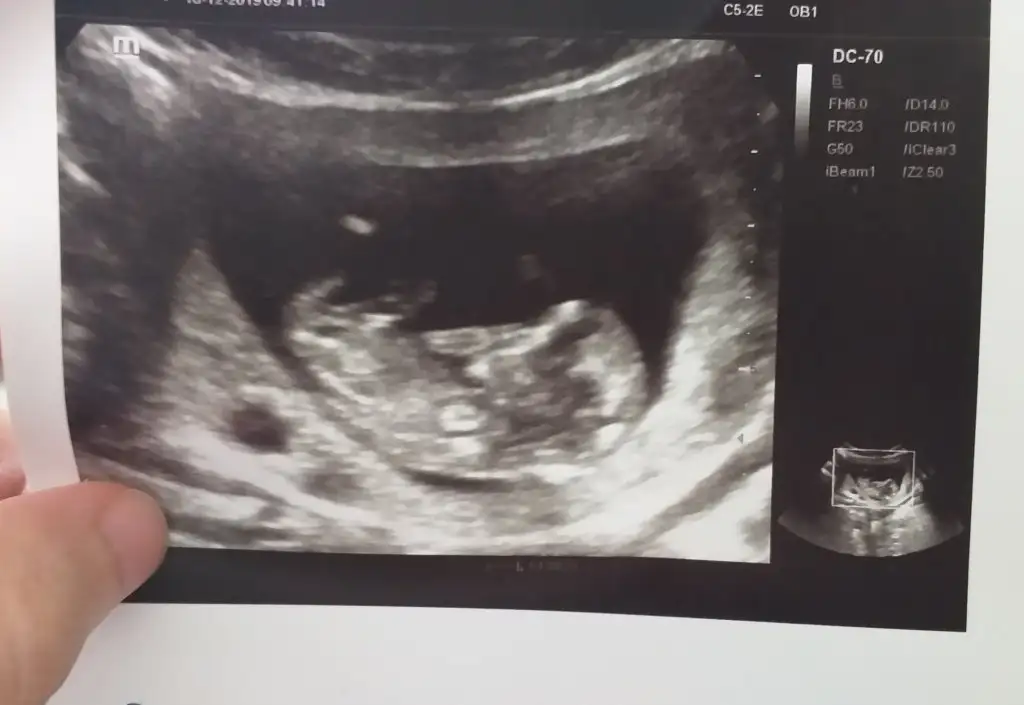

Erkek ve kız için 11 yada 12 hafta usg görüntüsü olmalı açıklamalar asagıda yazıyorrabbim herkesin gönlüne göre nasip etsin inşallah .. ecmain

[/B]Eki Görüntüle 473828 gordugunuz gibi ust taraftaki simgedende anlasildigi gibi eger cikinti paralel ise kiz

yok 30°lik bir aciyla yukari dogru bakiyorsa %99 oglunuz olacak demektir simdi bi kac ornek resimler daha koyacagim kiziminkide dahil

Eki Görüntüle 473829 bu bir erkek bebek genital nub cikintisi gayet yukarda

Eki Görüntüle 473831 simdi burada cikintilara bakin eger bel popo cizgisine paralel ise kiz

yok 30 derecelik bir aciyla yukari bakiyorsa erkek

yabancilarin hepsi biliyor bunu biz neden eksik kalalim gayet bilimsel simdi ellerinde11 12 13 ultrason fotografi olanlar alsin hemen baksin yada koyalim buraya yorumlayalim